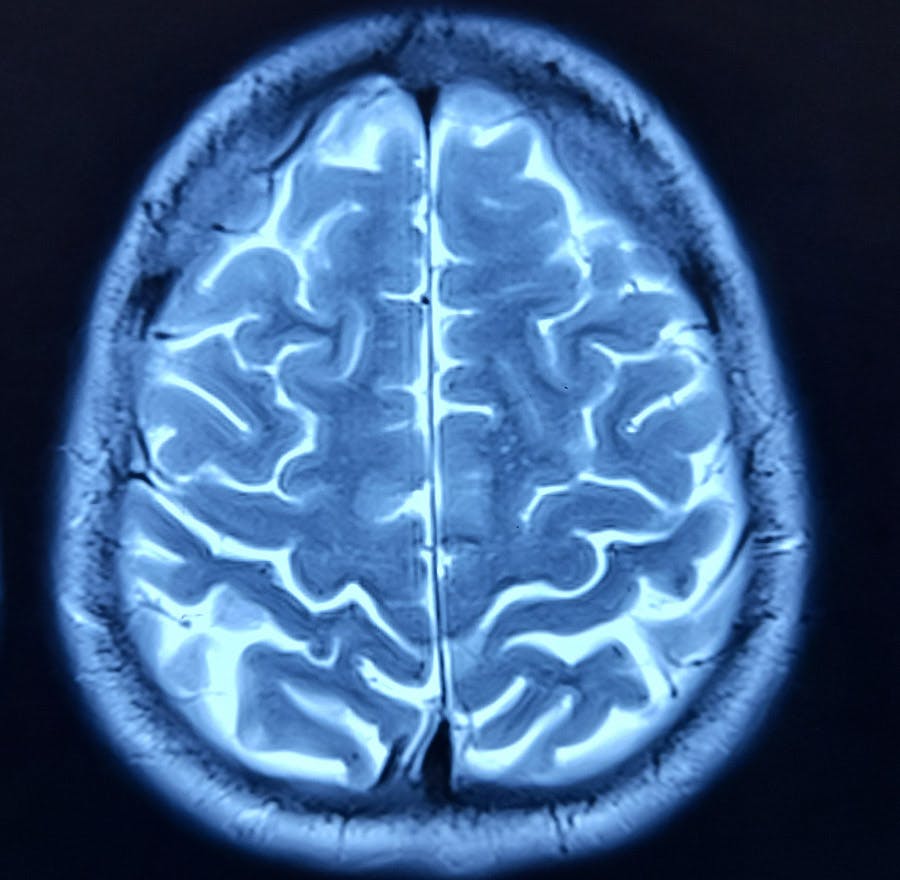

If you're struggling with persistent back or nerve pain and conservative treatments haven't provided sufficient relief, California Neurosurgical Institute offers cutting-edge spinal cord stimulator (SCS) therapy that could make a difference in managing your symptoms.

Spinal cord stimulators are effective in managing various conditions related to chronic back and nerve pain, including: